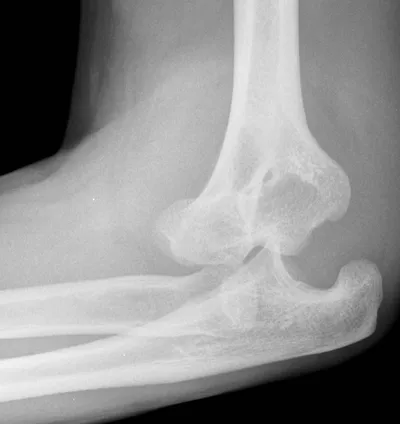

Radial neck fracture

Elbow

4/10/2026